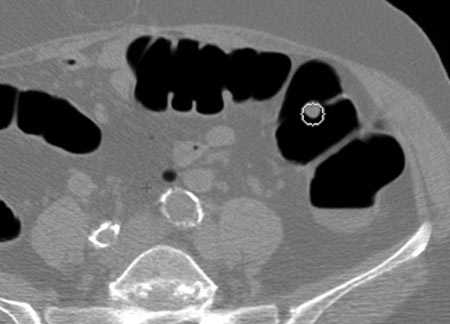

- Виртуальная колоноскопия (КТ-колонография) (раз в 5 лет) — мультиспиральная компьютерная томография (МСКТ), во время которой толстую кишку заполняют воздухом. Частота выявления с помощью этого исследования опухолей размерами более 1 см — 94%, полипов размерами 6–9 мм — 65%. Полипы менее 6 мм не обнаруживаются. Если во время КТ-колонографии обнаружен полип, чтобы его удалить, всё равно придется проводить эндоскопию. [9,10]

Снимок, выполненный во время КТ-колонографии